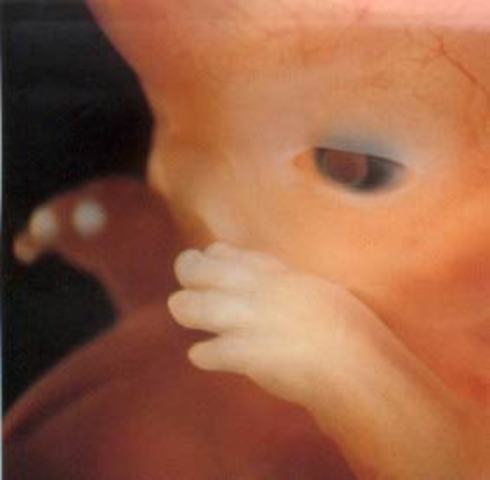

El feto necesita dormir y comienza a buscar una posición agradable para ello. En esta etapa se le suele encontrar chupando su pulgar. También oirá la voz, la respiración y los latidos del corazón de la madre.